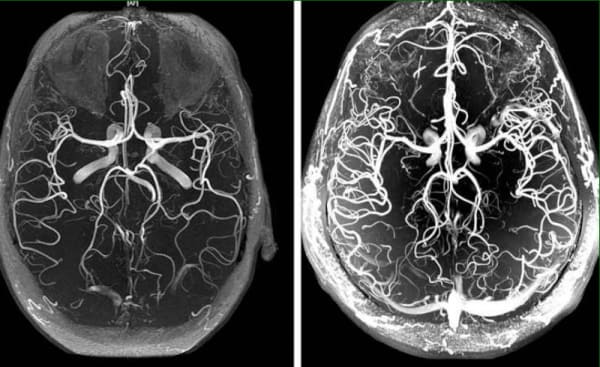

Ангиодистония сосудов головного мозга – это патологическое состояние, при котором нарушается тонус сосудов и нормальное кровообращение в тканях головного мозга. В этой статье вы сможете прочитать про её причины, механизмы и симптомы, при которых пора бить тревогу. А также про грозные осложнения этого коварного заболевания и про современный подход к решению этой проблемы, доступный каждому.

Ангиодистония сосудов головного мозга влияет на работоспособность всего организма. Из-за неадекватного кровоснабжения мозга, снижается общая работоспособность, появляется слабость, а важные системы организма начинают работать со сбоями.

В основе восстановления кровообращения сосудов головного мозга лежит очищение сосудов всего организма от накопленных загрязнений. Холестериновых бляшек, тромбов и кальциевой извести.

Восстановление кровообращения и чистка сосудов это комплексный процесс. Он затрагивает все сосуды организма и во много раз улучшает качество жизни.